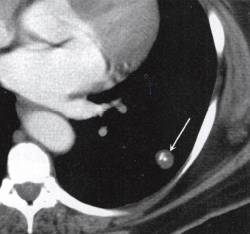

二、CT表现

爆米花样钙化征在CT影像中为不规则爆米花样改变的钙化灶,是错构瘤的特征性改 变。错构瘤的其他CT表现为:①肺内球形肿块,可分叶,直径多<4cm,但也可达10cm; ②肿块呈软组织密度,多较均匀;③可有钙化,呈爆米花状、点状、线状或环状;④肿块内 可有脂肪低密度影,CT值<-40HU,此为CT上错构瘤的重要诊断标准;⑤病变多邻近胸 膜或叶间胸膜。见图2。

图2爆米花样钙化征:左下肺边缘规则球形病灶,其内可见爆米花样钙化灶